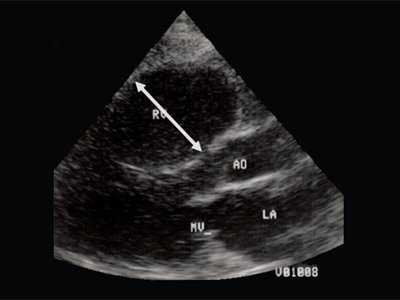

Характерными особенностями выраженной объемной перегрузки правого желудочка являются дилатация желудочка, при которой толщина миокарда не превышает верхней границы нормы, увеличение правого предсердия, парадоксальный характер движения межжелудочковой перегородки и увеличение амплитуды движения трикуспидального клапана (рис. 2, 3).

Рис. 2. Длинная ось сердца. Объемная перегрузка правого желудочка при дефекте межпредсердной перегородки. Объем сброса крови превышает 200% МОС. Отмечается выраженная дилатация правого желудочка.

Для левого желудочка признаком объемной перегрузки являются увеличение полости левого предсердия и желудочка, а также экскурсии межжелудочковой перегородки и миокарда задней стенки левого желудочка (рис. 4).